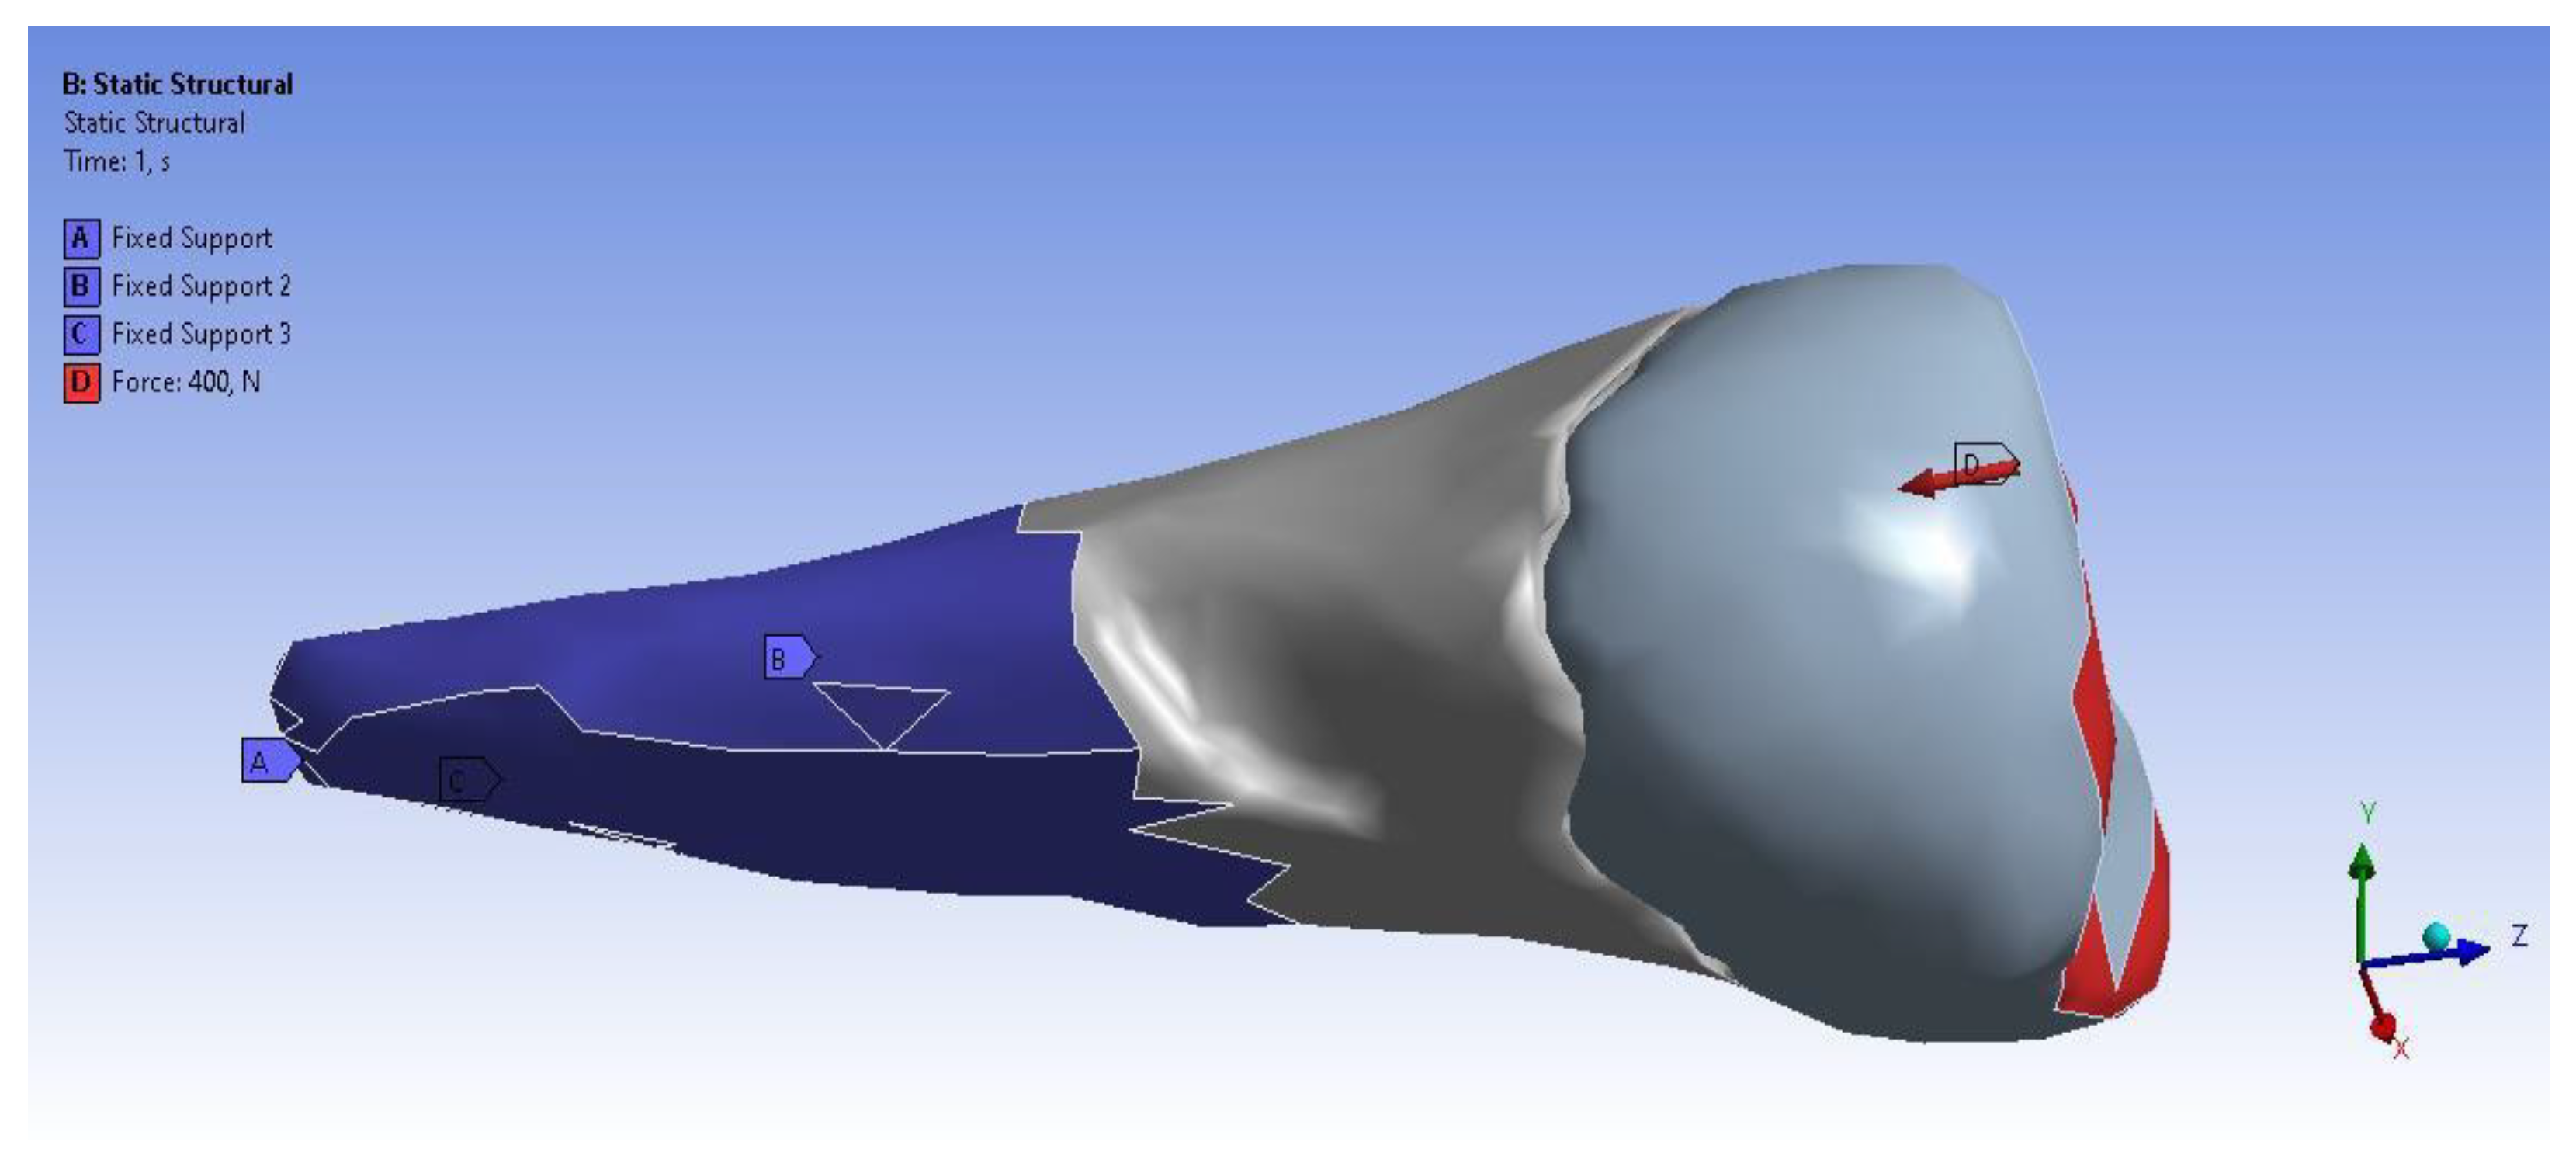

3. Finite Element Analysis (FEA) of Mandibular Right Premolars